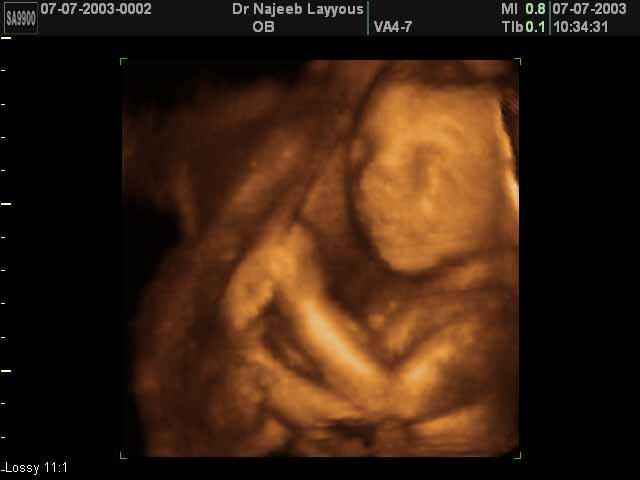

- صور جانبية لرأس الجنين

صور جانبية لرأس الجنين بجهاز الالتراساوند ثلاثي الأبعاد | الدكتور نجيب ليوس